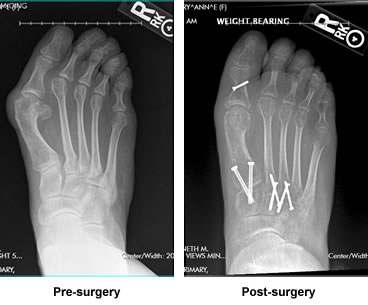

Previous Surgery Resulted in Years of Pain and Stress. Revision Surgery with Dr. Leavitt Eliminated Both Pain and Stress

For so many years, I have suffered from not only foot pain, but stress as well. As a woman who was not be able to be comfortable in anything but sneakers presented a lot of problems in my daily life. I would wander giant shoe warehouses, try on pair after pair, and leave more often than not, empty handed. I had had a previous surgical repair years ago with someone else, that actually caused more problems and despite wanting so very badly to seek treatment, I was so very scared to risk a bad result again, so I did nothing for many years.

From the moment I stepped inside your busy office and got a chance to meet with you and have you look at my x-rays, I felt immediately that I was in great hands. By talking with some fellow patients and various staff at the hospital, I began to feel even more confident. Everywhere I went, people had nothing but the most positive things to say about you. I finally felt ready to go through with the surgery.

You were honest with me, told me what to expect and after my weeks of recovery and rehab, I am so happy to say that my foot not only looks amazing, it is pain free as well. Thank you for your great skill, kind manner and for being the kind of doctor that truly cares about his patients. You have made such a positive change in my life!